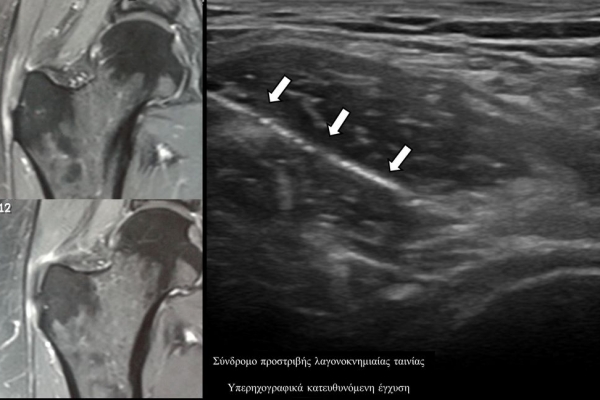

Υπό συνεχή υπερηχογραφική παρακολούθηση είναι δυνατόν να πραγματοποιηθούν κατευθυνόμενες εγχύσεις σε ορθοπαιδικές και ρευματολογικές παθήσεις. Αρχικά εντοπίζεται η παθολογική περιοχή και στη συνέχεια εξετάζεται η βέλτιστη οδός προσπέλασης. Ακολούθως γίνεται υπό άμεση και συνεχή υπερηχογραφική παρακολούθηση οι απαραίτητοι χειρισμοί και έγχυση φαρμάκων ακριβώς στη θέση της βλάβης.

Οι διαγνωστικές-θεραπευτικές εγχύσεις είναι δυνατόν να γίνουν σε μια πλειάδα μυοσκελετικών-ρευματολογικών παθήσεων όπως:

- σε ορογόνους θύλακες (πχ ώμου, αχιλλείου τένοντα, μείζονος τροχαντήρα κλπ)